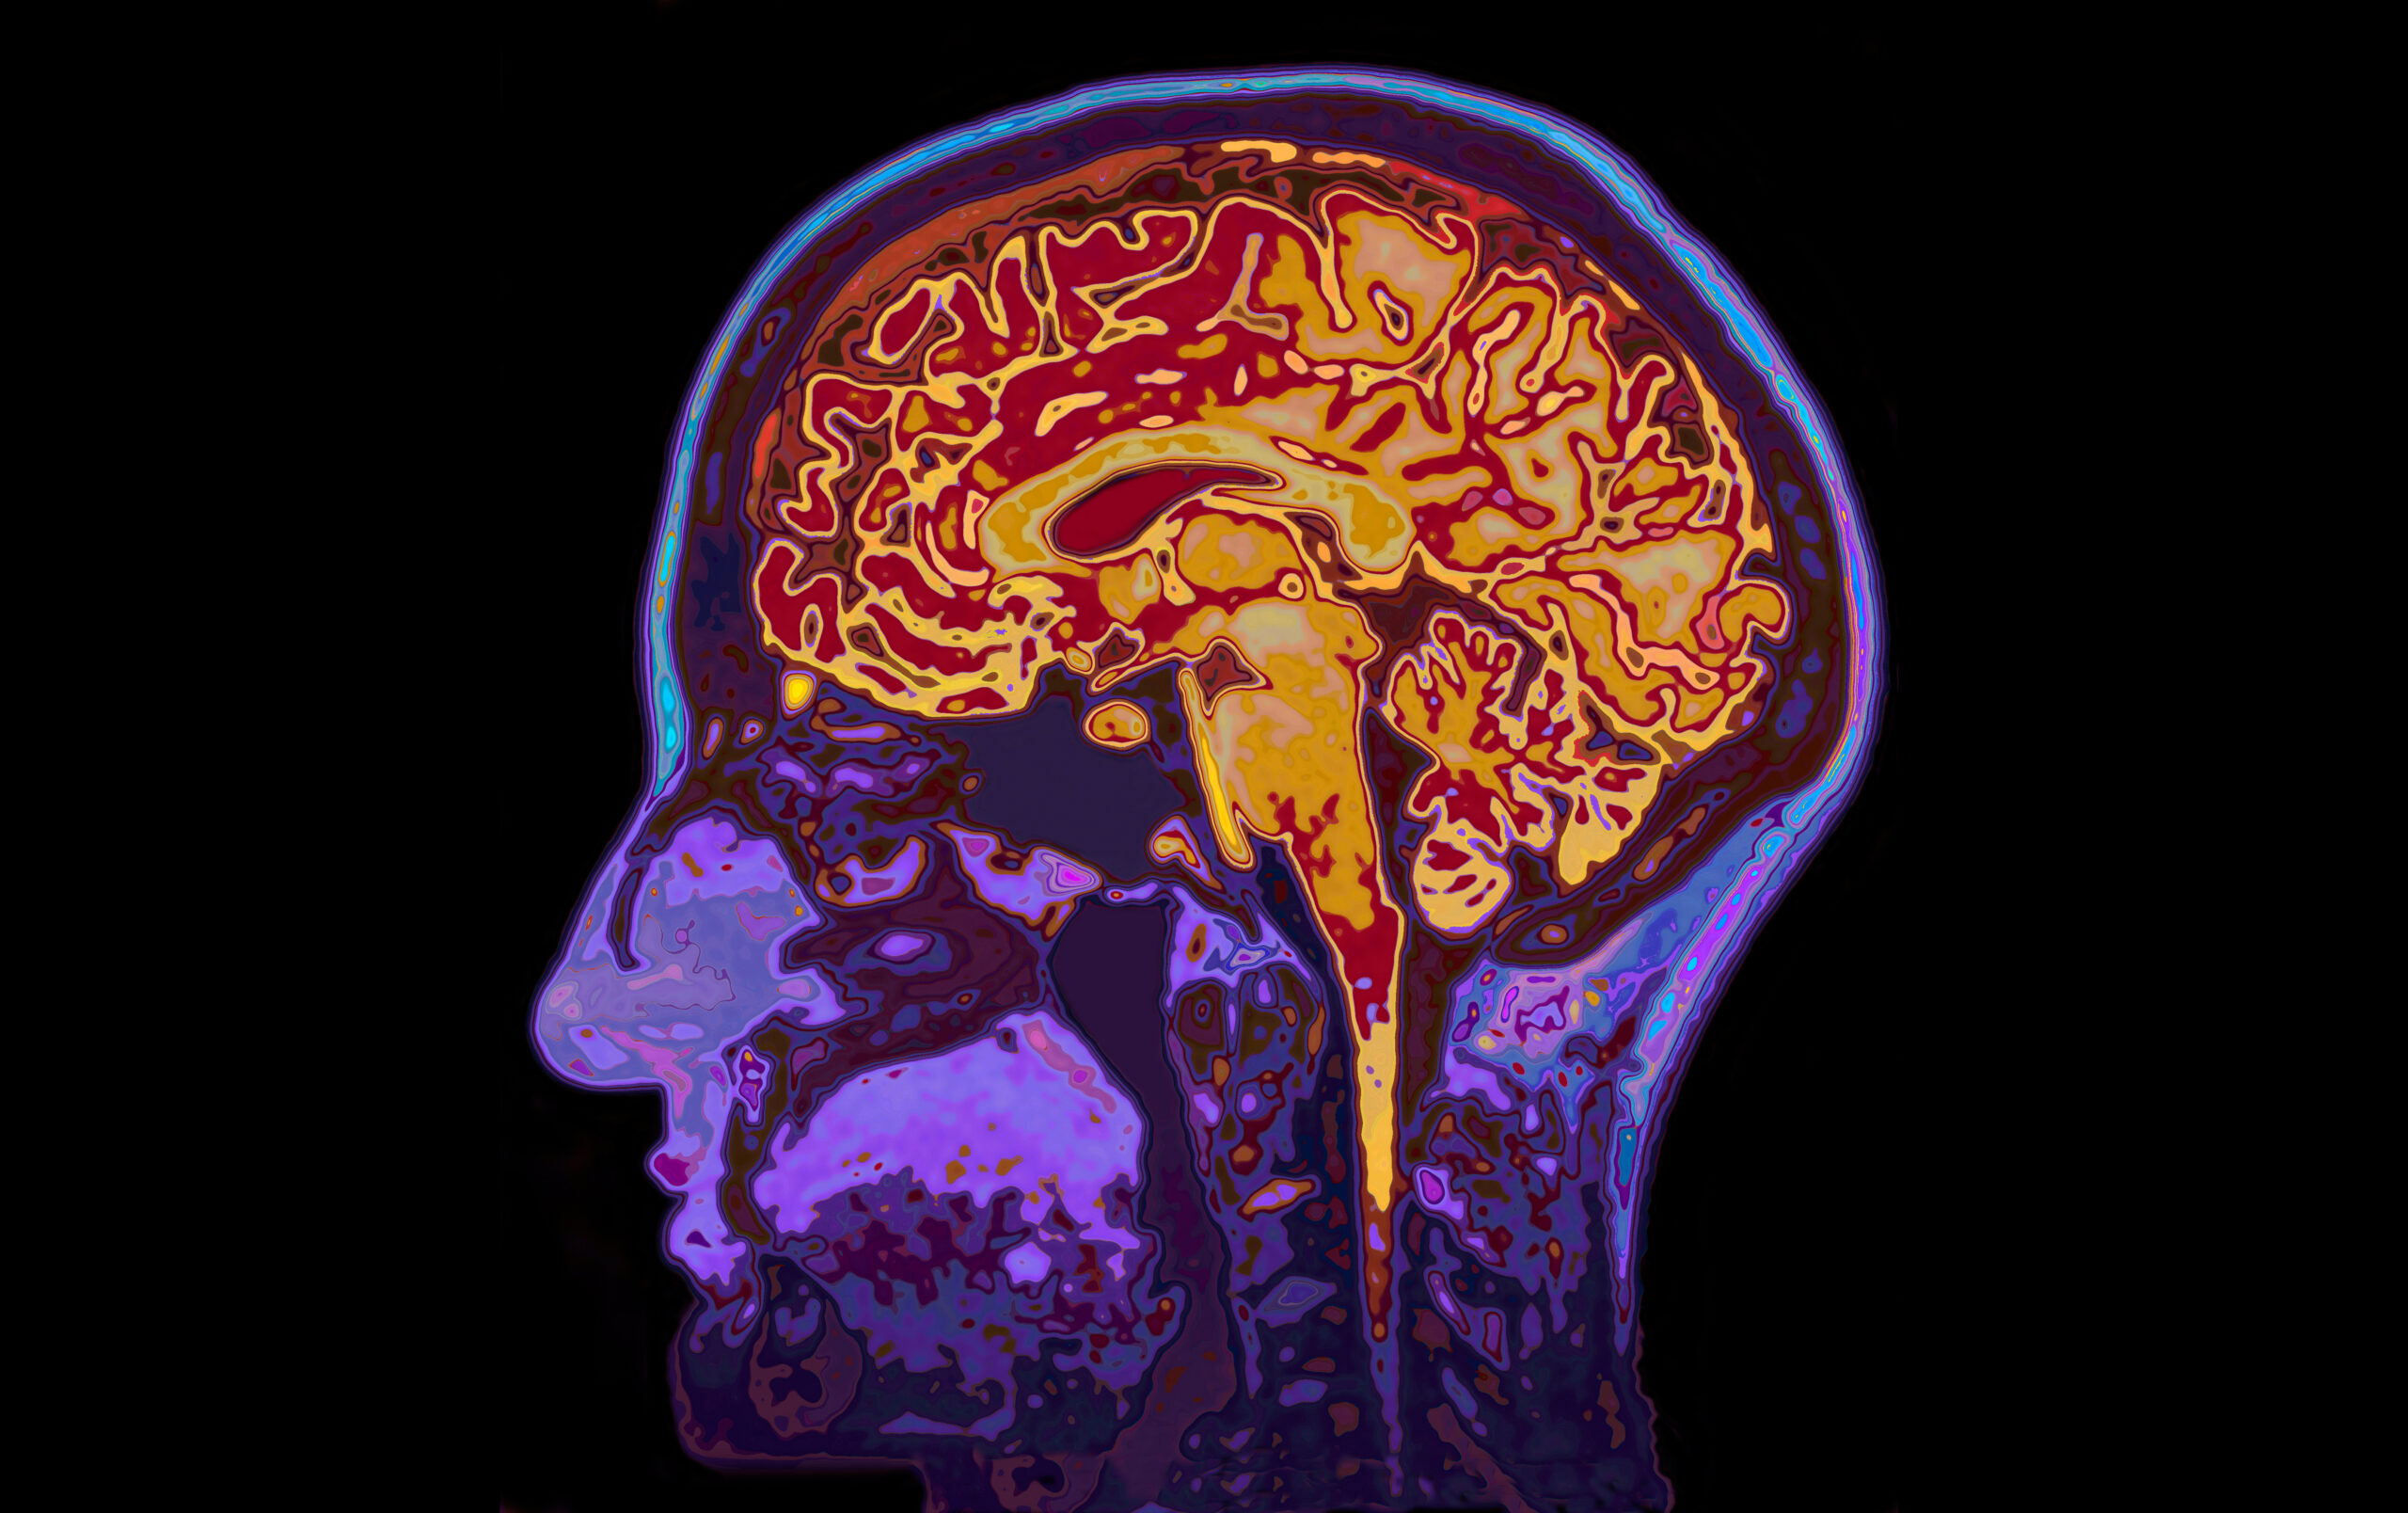

Accounting for 60% to 80% of all cases, Alzheimer’s disease is the most common type of dementia. This condition does affect everyone differently, but there are common symptoms that signal the onset of the disease. Because September is World Alzheimer’s Month, our team at HarborChase Senior Living is answering the question: What are the 10 warning signs of Alzheimer’s disease?